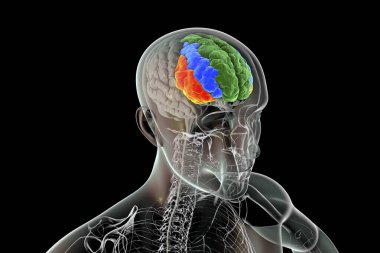

Tıbbi Konsept için sinir sistemi anatomisi olan 3D İnsan Beyni

MaviGrafikselresimlemeŞeffafİnsanSağlıkBaşıİlaçerkekkordonüç boyutlubiyolojikHücregövdeHastalıkİstihbaratİçeridebiyolojiBilimSistemAcıorgzihinomurgaelektronİşaretgörüntü oluşturmaanatomiomurilikbeyinMerkezGerginNörolojimikroskobikBeyin fırtınasıSıhhiyeanatomikSinirbeyincikcerebra3d oluşturmaüzerine siyahsinir hücresiBenzer İçerikler